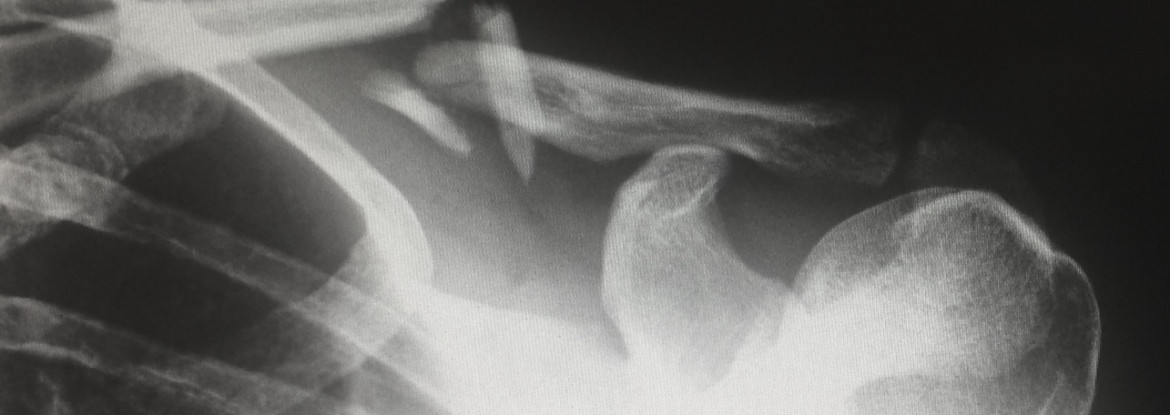

General Radiography uses x-rays to produce detailed images of the inside of the body. The x-ray machine generates the x-rays which penetrate through the body to produce an image.  It employs medical photography in which a snapshot is made of the specified body part.

During the exam, the patient is positioned so that the part of the body being imaged is located between the receptor and the x-ray tube. Common X-ray procedures include imaging of extremities (hand, foot) and the chest. Although best for bones, x-rays can see many soft tissue structures.